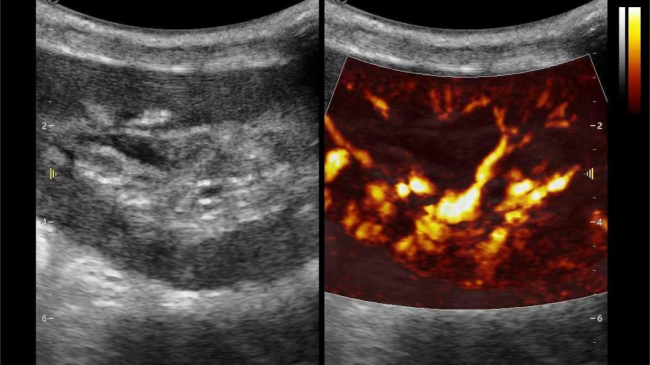

2) 可检测20-50μm级细小血管低速血流信号,能看清头发丝1/2粗细的微血管;

微米级超高分辨率血流信号显像

超微视血流显像评估肾移植术后灌注情况

这一项无创、无辐射操作简便且无需造影剂的黑科技,相当于用"高速摄像机"记录血液细胞的运动轨迹,让血管并发症"无处遁形。